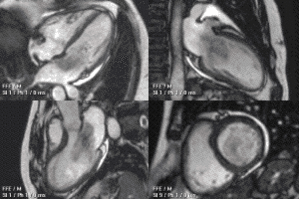

• магнитно-резонансная томография предоставляет информацию о размере, форме, поверхности и подвижности миксомы. МС обычно изоинтенсивны на Т1-взвешенных изображениях и гиперинтенсивны на Т2-взвешенных изображениях.